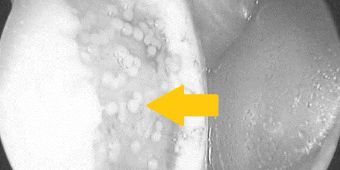

Knorpelzelltransplantation mit vielen runden Knorpelzellkugeln (Pfeil) am Knie. © Asklepios

Nach ca. 4-6 Wochen sind dann ausreichend Knorpelzellen vorhanden, um den Knorpelschaden optimal zu therapieren. Die Zellen liegen je nach Bedarf in einer Membran eingebettet oder als Knorpelzellkugeln (Sphäroide; siehe Bild) vor. In einem zweiten Eingriff werden die Zellen dann minimalinvasiv in den Schaden eingebracht. Am nächsten Tag beginnt dann der Rehabilitationsprozess. Auch wenn bei diesem Verfahren zwei Operationen notwendig sind, ist gerade bei großen Defekten mit der besten und stabilsten Gewebequalität zu rechnen.